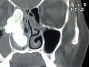

Burun tıkanıklığı ve baş ağrısı şikayeti bulunan Fatma Togar, ağrıları artınca Mengücek Gazi Eğitim ve Araştırma Hastanesi Kulak Burun Boğaz (KBB) Hastalıkları ve Baş Boyun Cerrahisi Kliniği'ne başvurdu. Endeskopi ve tomografi çekilmesinin ardından kadının yüzünün sağ bölümünde burun kanalı içerisinde cevizden büyük kemik tümörü olduğu belirlendi. Prof. Dr. Ümit Tunçel eşliğinde, Yrd. Doç. Dr. Fatih Turan ve ekibi, 4 saatlik bir operasyon yaptı. Operasyonda burun içerisinden endoskopik yöntemle tümöre ulaşıldı ve çevre dokulara zarar vermeden kitle genizden çıkarıldı.